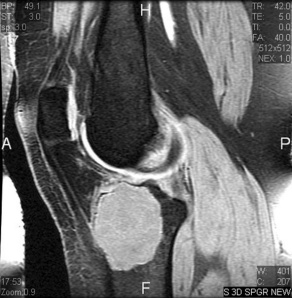

Giant Cell Tumor